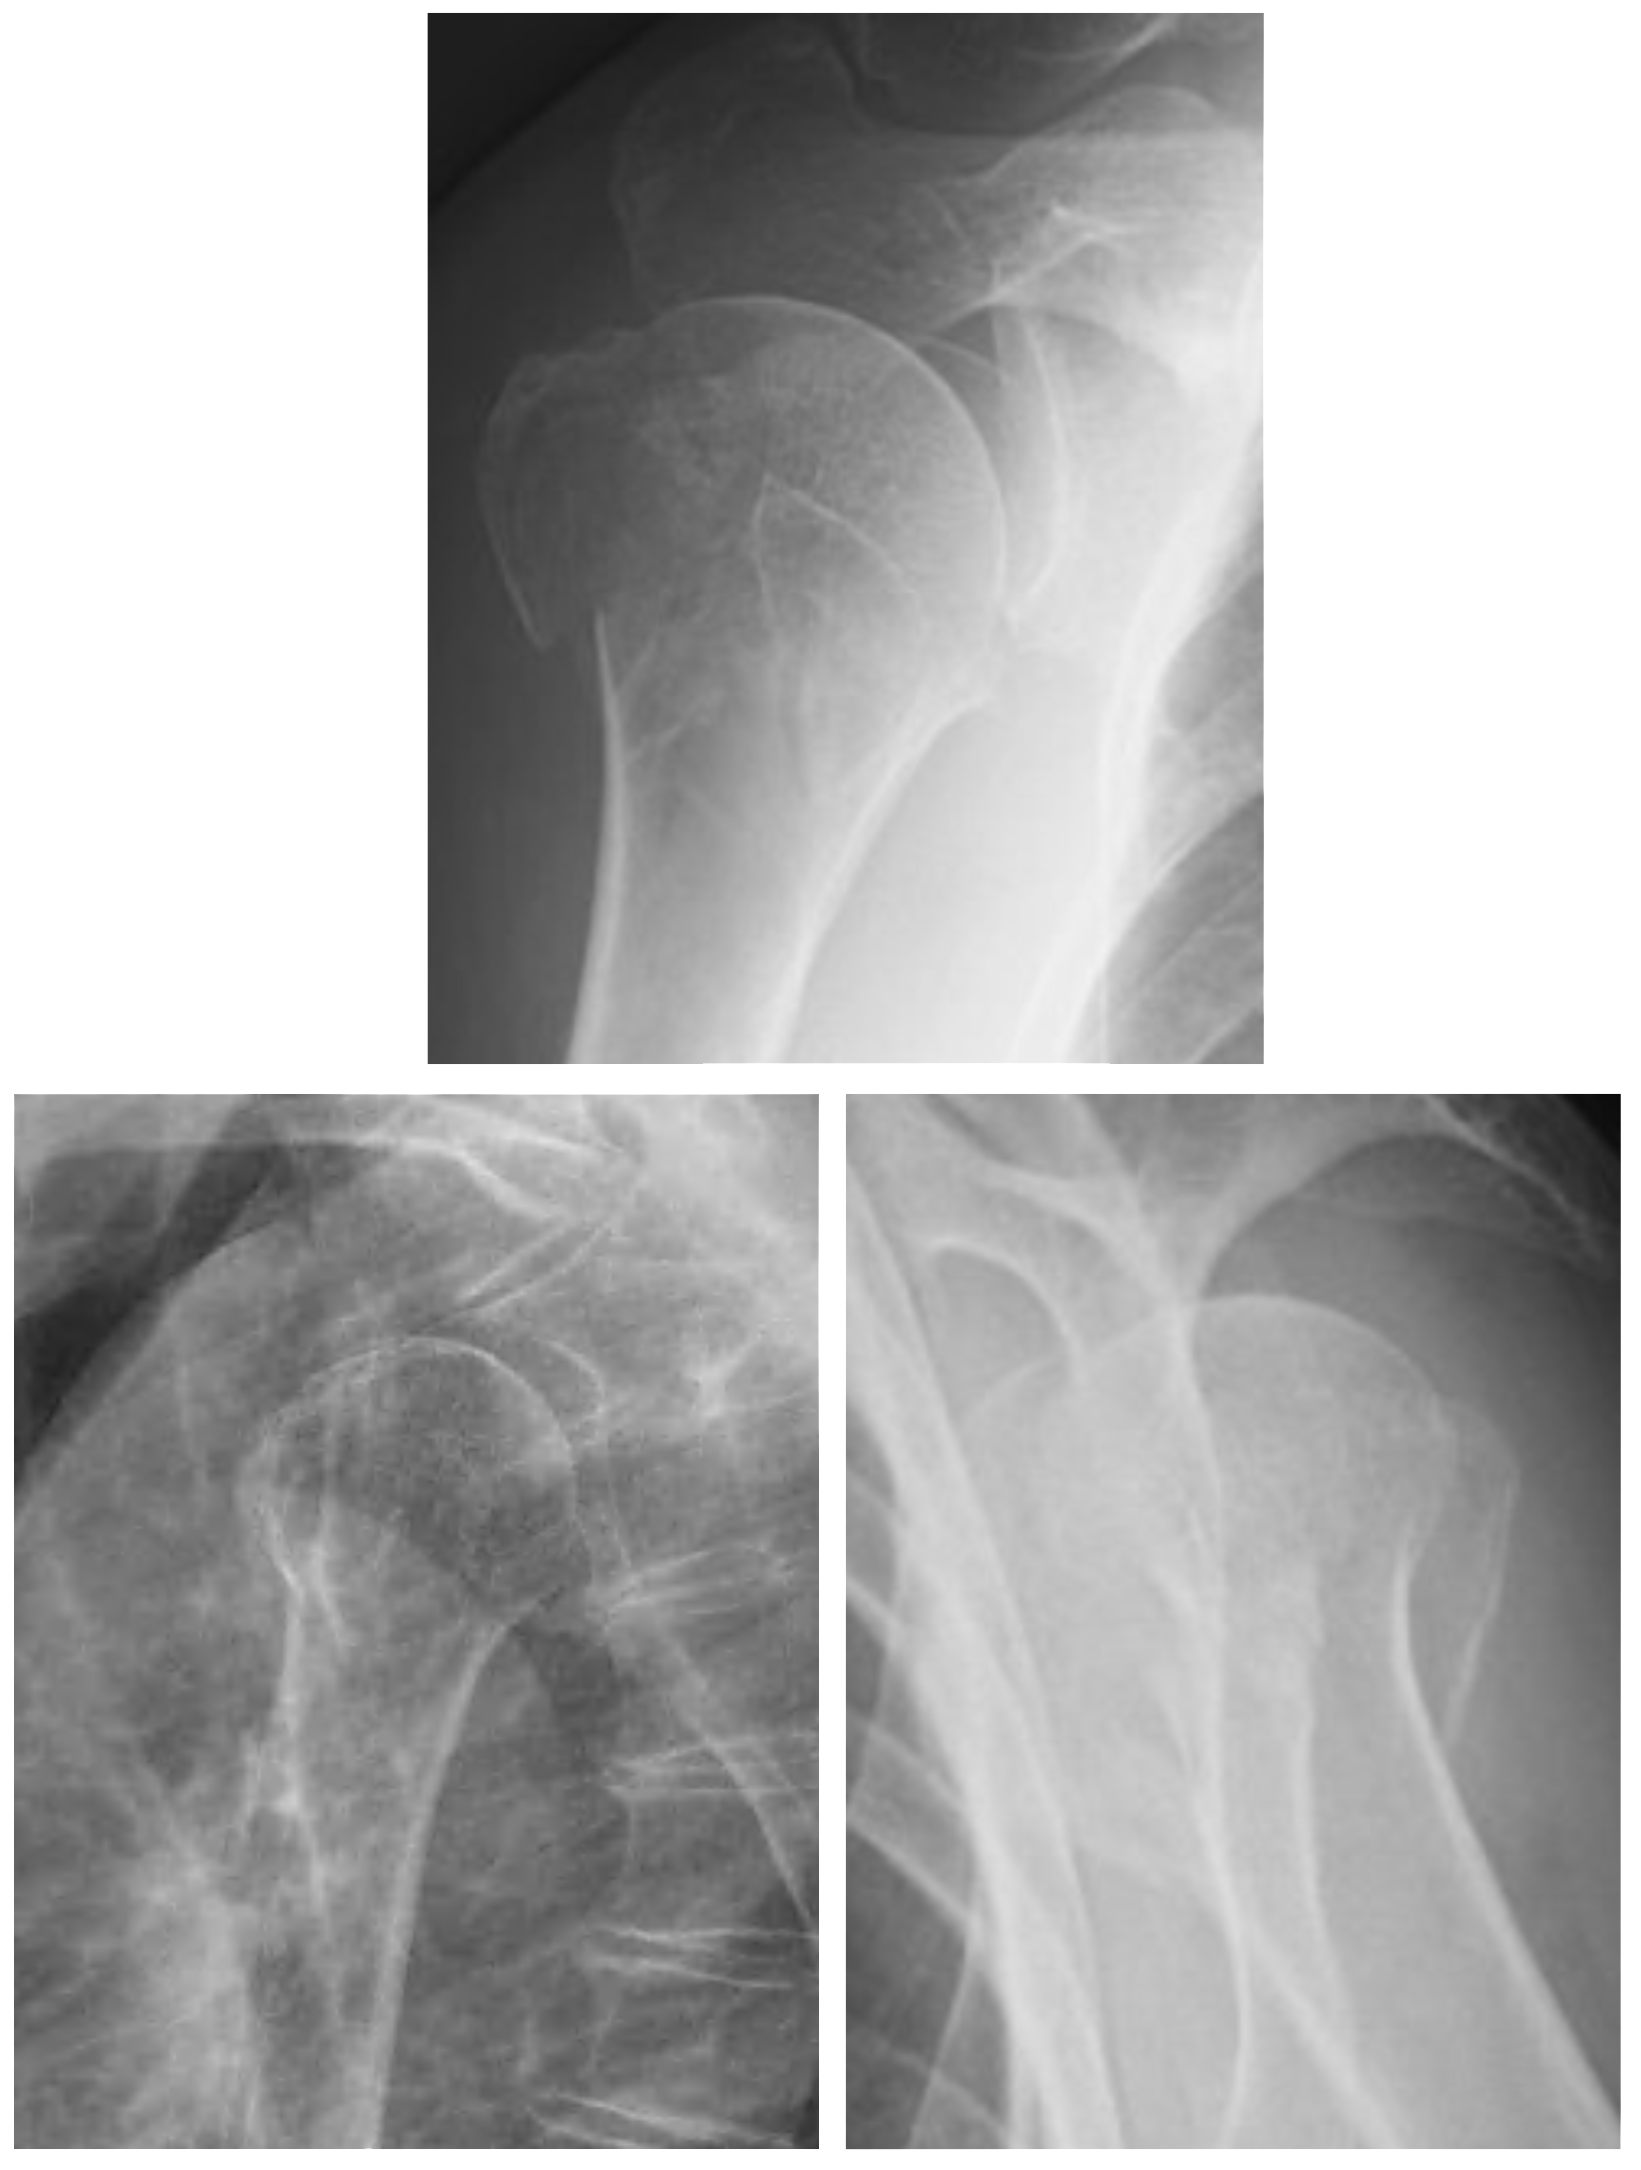

Pre-op

- 66 year-old female

- Proximal humeral fracture 6 months ago

- Initially conservative treatment

- Poor outcome

- Very limited function

- Severe pain (8/10)

- Mal-union/ necrosis